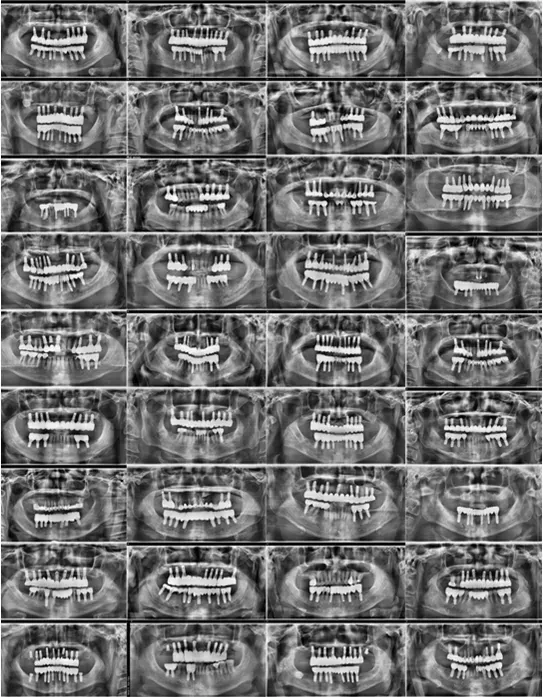

Full Implant Dentures

For those who have lost most of their teeth or found conventional dentures uncomfortable, full-mouth implants

can significantly transform your quality of life.

Full implant treatment is about results. At Feel Good Dental, many patients who have already undergone full implant treatment report high satisfaction with their chewing strength, stability, and comfort in daily life.